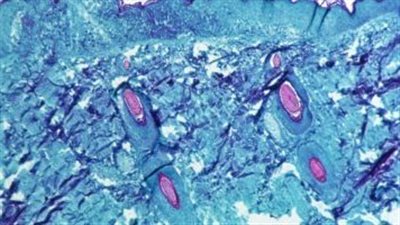

ولاية أسترالية جديدة تسجل أول إصابة بفيروس جدري القرود

الصحة الأسترالية تحذر من انتشار فيروس جدري القرود محليًا

أستراليا تسجل حالة جديدة بفيروس جدري القرود

أستراليا ترصد الحالة الثامنة بجدري القرود لمريض عائد من أوروبا

أستراليا تسجل الحالة السادسة من جدري القرود

عائد من بريطانيا.. أستراليا تعلن اكتشاف أول حالة إصابة بمرض جدري القرود